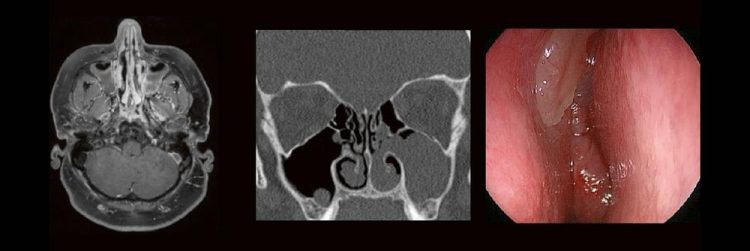

HNO & Radiologie: gemeinsam durch die NNH – ein Joint Venture (Webinar | Online)

Dr. med. André ReisbergDr. med Sebastian Plößl Die bildgebende HNO-Diagnostik macht es Anfängern nicht leicht. Die Anatomie ist komplex und weniger intuitiv als in anderen Körperregionen. Normvarianten erschweren insbesondere in den Nasennebenhöhlen den Lernprozess. Sobald pathophysiologische Zusammenhänge verstanden und wichtige klinische Aspekte verinnerlicht wurden, gelingt es einen praxistauglichen, belastbaren Befund zu erstellen. Wo muss ich…Continue reading HNO & Radiologie: gemeinsam durch die NNH – ein Joint Venture (Webinar | Online)